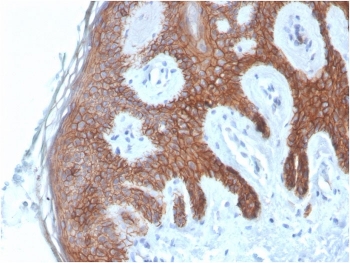

Cadherin 1 Antibody Skin IHC. Immunohistochemistry analysis of Cadherin 1 / CDH1 expression in FFPE human skin using clone CDH1/4585 antibody, showing strong membranous HRP-DAB brown staining in stratified epithelial cells of the epidermis with clear cell-cell junction localization, while underlying dermal tissue remains largely negative. HIER: boil tissue sections in pH 9 10mM Tris with 1mM EDTA for 20 min and allow to cool before testing. Signal highlights epithelial organization and adhesion-associated signaling within the epidermis.

IHC staining of FFPE human skin with Cadherin 1 antibody (clone CDH1/4585). HIER: boil tissue sections in pH 9 10mM Tris with 1mM EDTA for 20 min and allow to cool before testing.